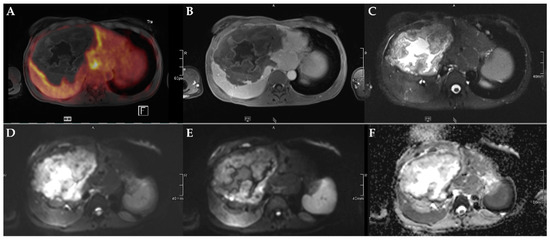

Figure 3.

45-year-old female patient with AE and involvement of liver segments IVa–VII and Kodama Type 3 lesion. Increased FDG uptake is observed at the lesion rim (A) with increased uptake of the contrast agent (B). High signal intensity is present in the central cystic parts in T2w imaging with fat suppression (C). Diffusion imaging demonstrates a high signal at a low b-value (b50) in the central parts of the lesion (D), a low signal at a high b-value (b800) (E), and high ADC values (F), indicative of no diffusion restriction.